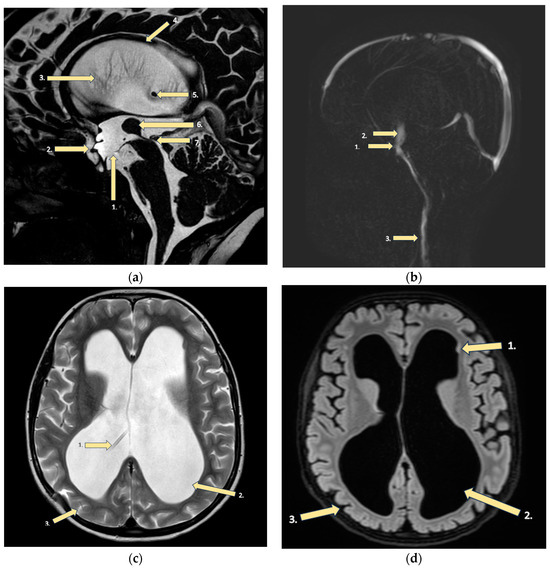

- Bar-Yoseph, R.; Livnat, G.; Guilburd, J.; Vachyan, A.; Ilivitzky, A.; Bentur, L. Intractable cough in a preterm infant with ventriculoperitoneal shunt. Pediatr. Pulmonol. 2013, 48, 405–407. [Google Scholar] [CrossRef]

- Huhndorf, M.; Peters, S.; Cordt, J.; Margraf, N.G.; Salehi Ravesh, M.; Jansen, O.; Synowitz, M.; Cohrs, G. Venous 3D phase contrast magnetic resonance angiography increases diagnostic certainty in children with ventriculoperitoneal shunt and suspected shunt failure. Clin. Neuroradiol. 2023, 33, 1067–1074. [Google Scholar] [CrossRef] [PubMed]

- Albugami, S.M.; Alwadi, K.W.; Alrugaib, A.K.; Alsuwailim, A.M.; Aljared, T. Prevalence and characteristics of shunt malfunction without ventricular size change at King Abdulaziz Medical City in Riyadh. Neurosciences 2021, 26, 31–35. [Google Scholar] [CrossRef]